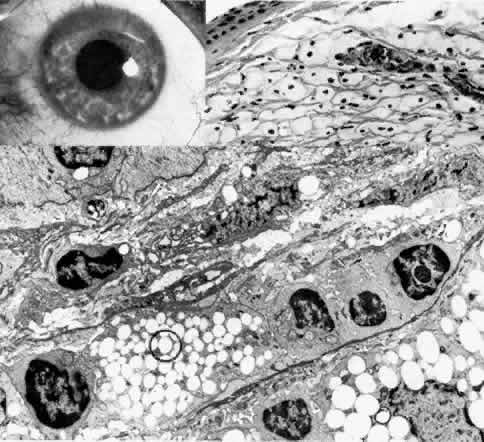

The appellation of map-dot-fingerprint dystrophy is appropriately descriptive of the biomicroscopically visible features of intraepithelial microcysts (dots), subepithelial ridges (fingerprints), and geographic opacities (maps) (Fig. 6; Color Plate 1D).49–66 Family studies have revealed a probable dominant inheritance for map-dot-finger-print dystrophy, with variable penetrance.67 Other clinical studies are more consistent with degeneration that is rather highly prevalent in the general population.56

Fig. 6. Map-dot-fingerprint dystrophy. Top left. Clinical photograph of a 37-year-old man with non-traumatic erosions shows characteristics of map dystrophy with superficial geographic haze interrupted by clear areas. Top right. In the dot form of Cogan's mycrocystic dystrophy, superficial, opaque cysts are evident within the epithelium. Upper middle. Three variants of fingerprint dystrophy show subepithelial ridges, particularly enhanced by retroillumination. Lower middle left. Phase-con-trast microscopy of map dystrophy shows fibrous tissue (*) interposed between epithelium and Bowman's layer (B) (paraphenylenediamine, × 1000). Lower middle center. Phase-contrast microscopy of dot dystrophy shows an intraepithelial pseudocyst evolving from disintegration of desquamating cells (paraphenylenediamine, × 1200). Lower middle right. Phase-contrast micrograph of fingerprint dystrophy illustrates fingerlike intraepithelial extensions of aberrant fibrocellular material anterior to the normal-appearing Bowman's layer (B) (paraphenylenediamine, × 800). Bottom. Transmission electron micrograph in these disorders consistently finds multiple laminations of basement membrane material (*) with reduced hemidesmosomes (small circle) and increased anchoring fibrils (large circle) beneath epithelium (E) (× 40,000). (Upper middle, slit lamp photographs courtesy of Lawrence Hirst, MD)

The symptoms of recurrent erosion can become prominent in early adulthood through middle age and range from mild irritation to painful, early-morning erosive episodes. Irregular corneal astigmatism with complaints of distortion or “ghost images” may also occasionally develop secondary to plaquelike accumulations of subepithelial cellular debris, basement membrane, and collagen.

The degree of clinical symptoms, however, often do not parallel the extent of abnormal slit lamp findings. Because of the presumed primary abnormality in the epithelial basement membrane, even minor trauma may cause a major epithelial breakdown, with impaired subsequent healing. In a patient who has had a trivially traumatic or seemingly spontaneous erosive episode, meticulous examination of the symptomatic eye, as well as the fellow eye, should be performed in an attempt to disclose an underlying dystrophy. Careful inspection of the fluorescein-stained tear film for localized irregularity or instability, and retroillumination at high magnification through a dilated pupil are helpful in uncovering these often subtle abnormalities in a patient who complains of spontaneous irritation.

Many ultrastructural studies of map-dot-finger-print dystrophy have disclosed a discontinuous multilaminar, thickened basement membrane under the abnormal epithelium.49,64,65 Sometimes this abnormal basement membrane contains an admixture of collagenous and cellular debris suggestive of prior breakdown episodes. More widespread coalescence of this subepithelial material gives the clinical maplike picture. Other configurations of aberrant basement membrane and fibrillar collagens can be found extending in ridges into the epithelial layers, thereby explaining the fingerprint pattern. Epithelial microcysts are actually pseudo-cystic collections of cellular and amorphous debris within the epithelial layer. Their shape changes with time since they are formed from entrapped cellular material deeper within the epithelium. As they travel to the surface, they may coalesce with other cysts and finally break through the surface, giving rise to an irritative episode.

The primary defect in map-dot-fingerprint dystrophy is presumably the synthesis of abnormal basement membrane and adhesion complexes by the dystrophic epithelium. Unable to form proper hemidesmosomes or anchoring fibrils, the epithelium undergoes recurrent subclinical or overt episodes of dysadhesion. This periodic “lift-off” allows debris to accumulate subepithelially, providing an even less adequate substrate on which the already abnormal basement membrane must form. Moreover, intraepithelial extensions of abnormal basement membrane and collagenous material may block the normal surface migration of maturing epithelial cells, allowing the formation of encysted collections of debris. Thus, the cycle is to a degree self-perpetuating, with primary faulty epithelial adhesion secondarily causing abnormal epithelial maturation which, in turn, exacerbates the accumulation of abnormal basement membrane and collagenous debris and leads to further worsening of epithelial adhesion. Gentle débridement of severely aberrant epithelium and, in some instances, superficial keratectomy to remove subepithelial debris is an aid to conservative therapy with lubricants, hypertonic saline ointment, patching, or bandage soft contact lens.

Similar fingerprint, map, and intraepithelial microcyst changes may develop after traumatic, infectious, or ulcerative conditions, and particularly in cases of chronic epithelial edema where repeated lift-off of the epithelial sheet allows the interposition of material that can again thwart the development of proper basement membrane adhesion complexes.